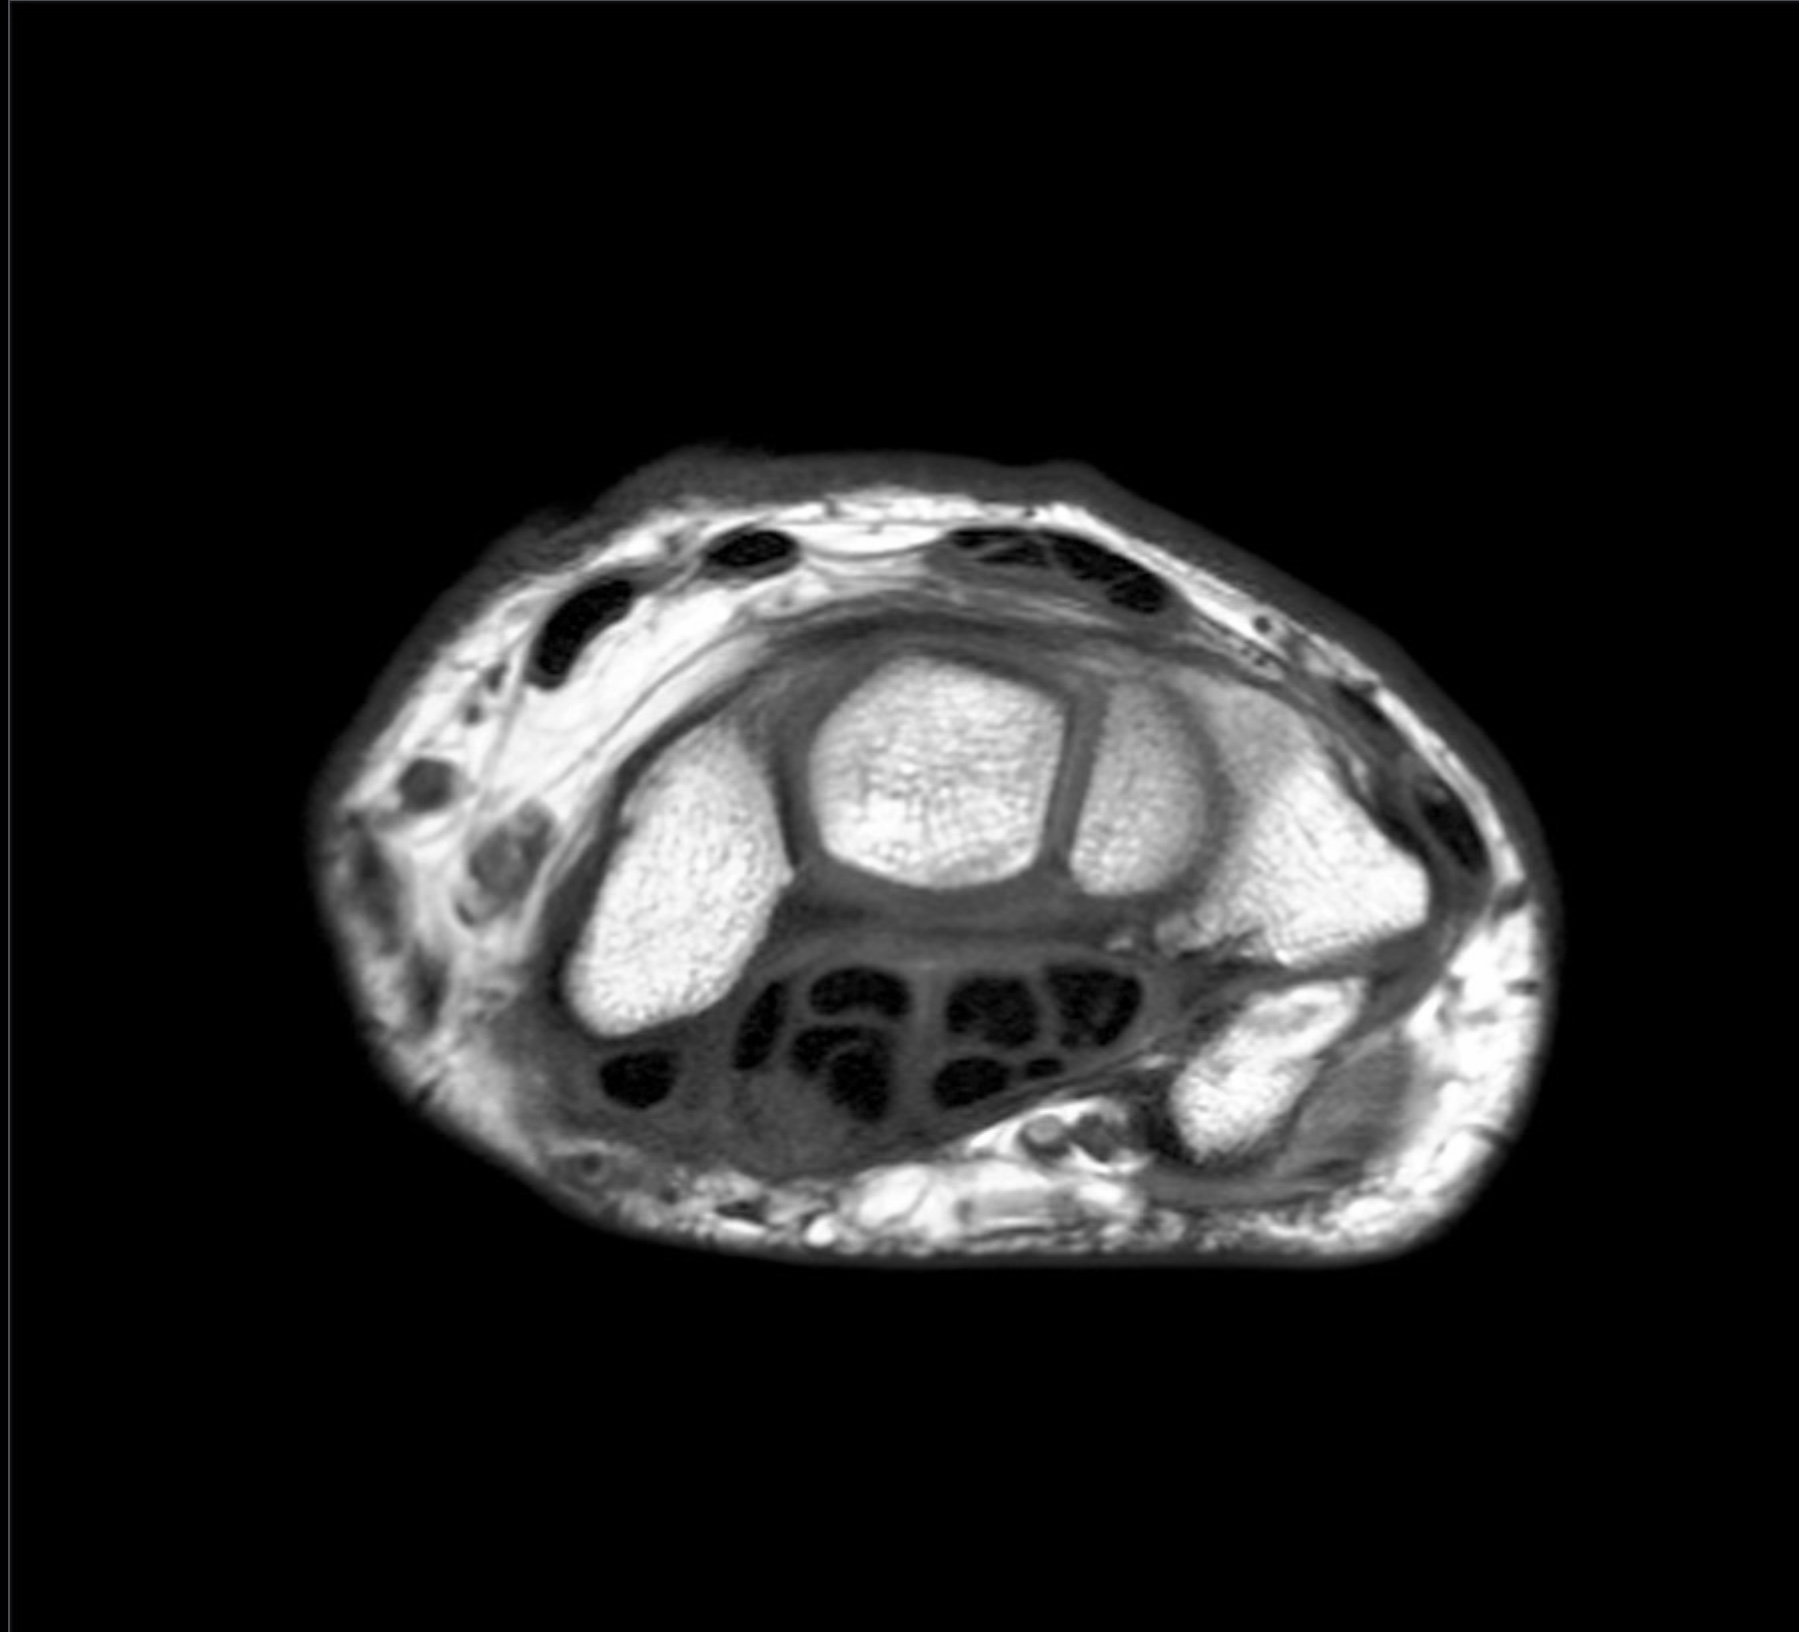

1. A 54-yr-old woman presents with atrophy of the thenar eminence and a lack of sensation on the palmar surface of the radial 3.5 digits. Testing confirms carpal tunnel syndrome with a positive Phalen’s test and Tinel’s test. Describe the boundaries and contents of the carpal tunnel. In your answer, be sure to include the function and innervation of the muscles whose tendons pass through the carpal tunnel. (G. Francis)